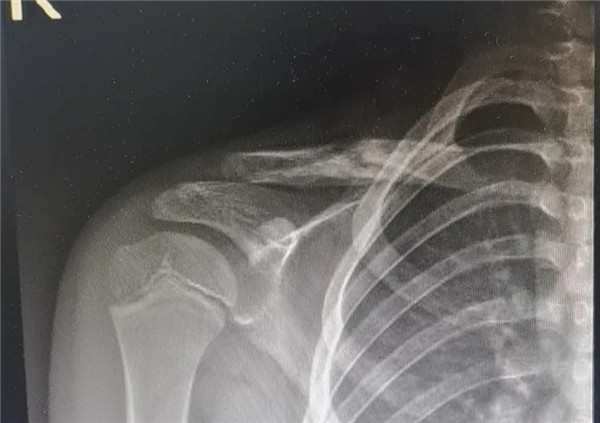

6月3日,在征得家屬同意,洋洋的身體符合手術(shù)指征后,洋洋接受了右鎖骨骨折切開復(fù)位內(nèi)固定術(shù),手術(shù)由應(yīng)文世主任主刀。術(shù)中可見右鎖骨呈粉碎性骨折,骨折端移位明顯。一個小時后,手術(shù)順利結(jié)束。術(shù)后,洋洋恢復(fù)良好,6月9日順利出院。一個月后,在來復(fù)查時,洋洋的媽媽帶來了一面錦旗送予應(yīng)文世主任及手外科周小君副主任,以感謝他們的高超技術(shù)及優(yōu)質(zhì)服務(wù)。

復(fù)位后